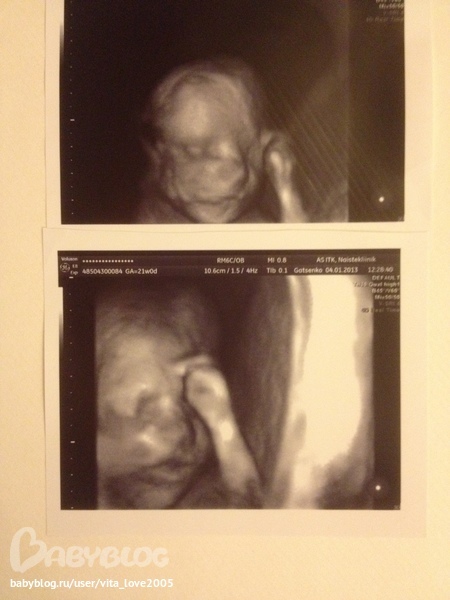

Все показали все змерили!)) Ручки, ножки, все пальчики, плечики,бедрышки, голова, пузик вообщем все!)) Сидим мы в позе лотоса, как йог!)) Голова находится под моими левыми ребрами на 2 пальца ниже! Весим мы 401 грамм. от головки до попки 20 см. Сказали здоровенькие и все хорошо ровно по сроку даже чуть больше на пару дней!!)) Мы пузатики, такие класные!!!

Врачь сказала, что у нас приличное хозяйство, очень все четко было видно!! Папа наш гордится, вот это подарок ему в день его рождения!))) А вот и мы, для фото врачь включила программу 4D:

Сестра засняла на видеокамеру(это не запрещено) как все у нас смотрели, и что интересно, я сейчас пересматриваю на ночь это видео, все настолько четко,ощущение что я там в кабинете лежу и смотрю на монитор!)) Это офигенно!!!!!!!!)))))) Теперь мы запишемся на приеме у врача на УЗИ 4D на 25 неделе!! Там запишут диск и сделают хорошие фото!))